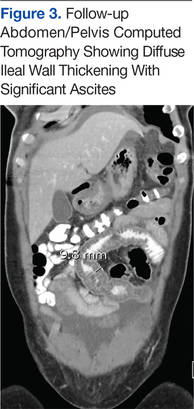

Six weeks after her initial presentation, the patient presented to the ED for the third time with the same symptoms. A CT scan again displayed diffuse ileal wall thickening with significant ascites; slightly worse than the image from initial presentation (Figure 3).